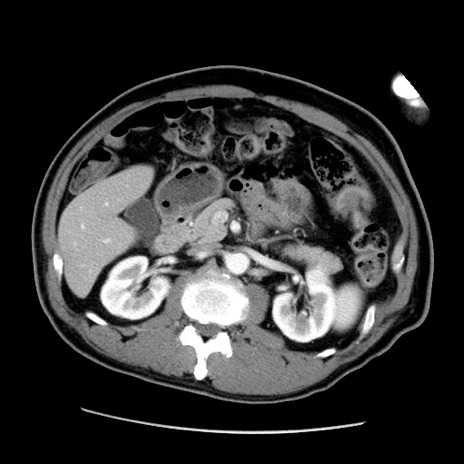

症例22(横断像)

【症例】50歳代男性

【主訴】腹痛

【現病歴】AVMからの被殻出血のため回復期リハ病棟入院中。 本日午後3時頃急に下腹部痛が出現した。

【既往歴】AVM、被殻出血、虫垂炎、高血圧

【身体所見】意識晴明、左半身不全麻痺、会話の理解は良好、36.5°C、腹部:膨隆、全体に板状硬、下腹部正中に圧痛点あり、反跳痛-、筋性防御不明、右下腹部にope scar

【データ】WBC 9400、CRP 0.06